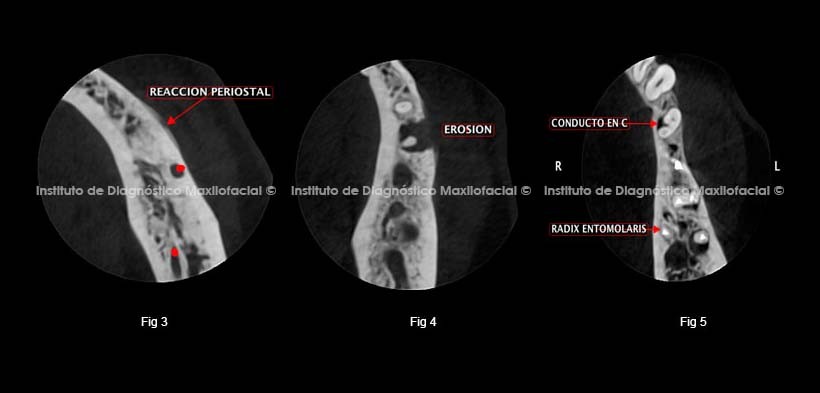

En los cortes axiales se puede observa a nivel de pieza dentaria 3.4 la reacción periostal (Fig. 3) y aumento de la densidad ósea circundante asociado a un proceso infeccioso, además se puede observa la erosión de la tabla ósea vestibular (Fig. 4)

En la corte axial se puede observa la variante anatómica de la primera premolar inferior – conducto en C (variante anatómica) además se puede observa en pieza dentaria 3.6 la presencia de una raíz supernumeraria orientada hacia lingual (RADIX ENTOMOLARIS) con obturación de canal radicular aparente se procedió a evaluar dichos hallazgos asociados al proceso infeccioso. (Fig. 5)